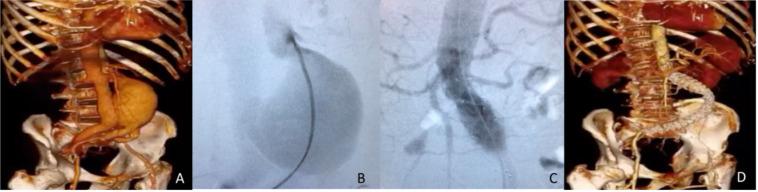

Ruptured abdominal aortic aneurysms (RAAA) evolving aortocaval fistula (AF) can have catastrophic hemodynamic effects. Surgical repair is imperative, but the optimal technical approach is still under debate. Our objective is to present 3 cases treated with endovascular repair (EVAR) at a University Hospital. Case #1, a 71-year-old man presenting a 7.1cm RAAA with AF, repaired with a monoiliac stent graft and femoral-femoral bypass; Case #2, a 76-year-old man presenting a 9.9cm RAAA with AF, repaired with a bifurcated stent graft; Case #3, a 67-year-old man with previous history of EVAR, presenting a type 3 endoleak with late rupture related to AF, repaired with a tubular stent graft. All cases unfolded with delayed recovery and significant complication rates, although AF symptoms had resolved by hospital discharge. EVAR techniques for AF may require secondary interventions but are feasible, despite the lack of consensus, considering the rarity of this RAAA presentation.

破裂性腹主动脉瘤(RAAA)并发主动脉腔静脉瘘(AF)可产生灾难性的血流动力学影响。手术修复势在必行,但最佳技术方法仍存在争议。我们的目的是介绍在一家大学医院接受血管腔内修复(EVAR)治疗的3例病例。病例1,一名71岁男性,患有7.1cm的RAAA并伴有AF,采用单髂支支架移植物和股-股旁路进行修复;病例2,一名76岁男性,患有9.9cm的RAAA并伴有AF,采用分叉支架移植物进行修复;病例3,一名67岁男性,既往有EVAR病史,出现与AF相关的3型内漏并晚期破裂,采用管状支架移植物进行修复。尽管所有病例在出院时AF症状均已缓解,但恢复均延迟且并发症发生率较高。尽管对于这种RAAA表现缺乏共识,但针对AF的EVAR技术可能需要二次干预,但仍是可行的,因为这种情况较为罕见。